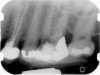

Fig 1. Preoperative radiograph showing apical bone loss.

Figure 1

Clinical procedure: If apical bone loss is present (Figure 1) a collagen/gelatin sponge (eg, Gelfoam®, Pfizer Inc., www.pfizer.com) can be placed apically so that the MTA can be delivered to the desired working length. (Any other surgical resorbable sponge would also work, such as OraPlug® [Salvin Dental Specialties, www.salvin.com], Surgifoam® [Midwest Dental, www.mwdental.com], or Surgispon® [Aegis Lifesciences, www.surgispon.com]). This is done by taking a small piece (2 mm x 2 mm) of the resorbable sponge and pushing it down to and through the root apex with an endodontic file. Once this is done, MTA is packed down the canal with a custom-fitted cone. The clinician can use a rubber stopper on the gutta-percha cone to know the exact length of MTA placed in the apical third (Figure 2). Once the apical third is sealed with 3 mm to 5 mm of MTA, the remaining coronal canal space can be back-filled using a warm gutta-percha technique (Figure 3).